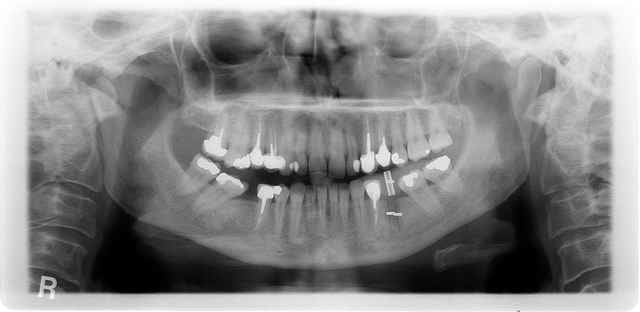

pour changer de sujet

un échec d'endo.

première consult en 3/2009 atteinte de 35

dépose de la ccm repirse d'endo repose de la ccm tenon raccourci

mais évolution+++ de la lésion qui m'a conduit à l'avulsion de la dent en septembre curetage soigneux et mise en place de : rien

en janvier pano de controle avec petit repère (tige maillefer recoupée à 10mm) dans du silicone

janvier pose d'un natéa en 4.1*10

pas de photo désolé